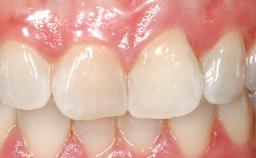

A 30-year-old female patient had lost tooth 21 and was referred to our clinic for consultation and treatment. Due to advanced apical infection, tooth 21 had been extracted two months earlier at another clinic and an acrylic-resin tooth had been bonded to the adjacent teeth. The patient desired implant treatment to avoid any damage to the adjacent natural teeth. While the patient had no history of any systemic disorder, she was a heavy smoker and exhibited medium to advanced periodontitis in the entire jaw. After the initial treatment to achieve a pocket probing depth of less than 4 mm and no bleeding on probing, a decrease in the height of the papillae mesial and distal to the extraction site and overall gingival recession were observed.

Soft Tissue Anatomy Intact Defective

Soft Tissue Contour and Volume Slightly compromised